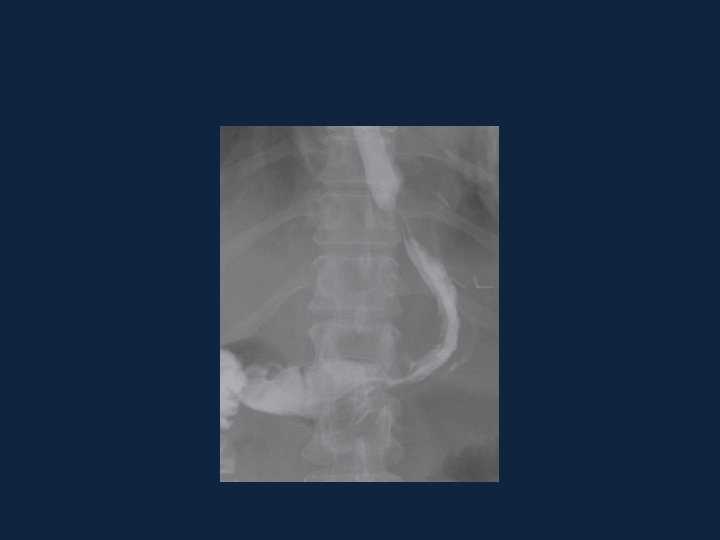

Gastrografin swallow studies demonstrating staple line leaks (a), focal leak (b), and leaks with contrast dissemination in the abdominal cavity